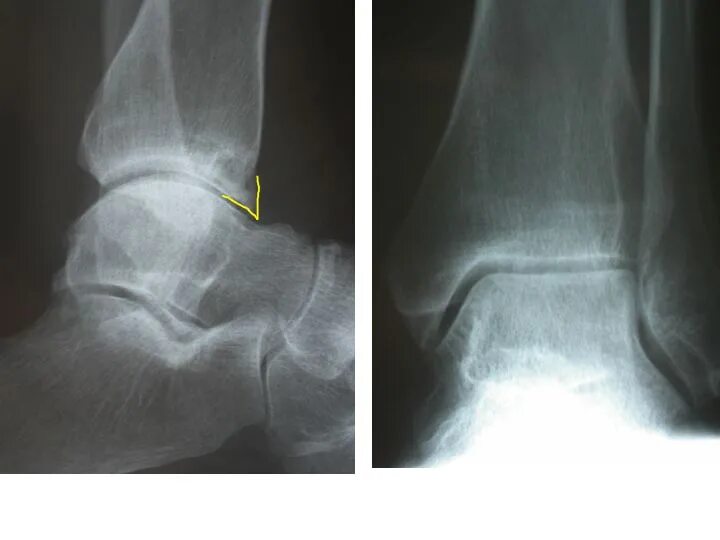

Синовит голеностопного таранного сустава